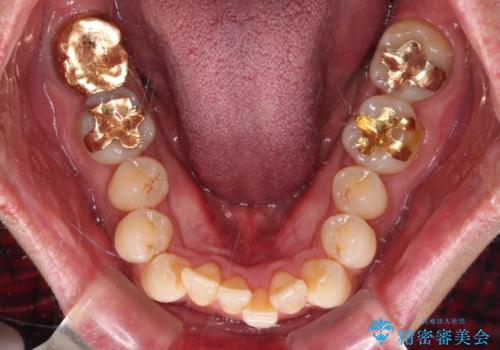

- 口元の突出感を気にして来院された患者様です。

強い咬合力と上顎前歯の傾斜により前歯が突出し、唇が閉じにくい状況であったため、上下左右の第一小臼歯4本を抜歯し、ワイヤー装置にて矯正治療を行うこととしました。

非常に咬合力が強いため、抜歯したスペースが閉じるのか不安でしたが、順調に歯が移動し、予定よりも早く治療を終えることができました。